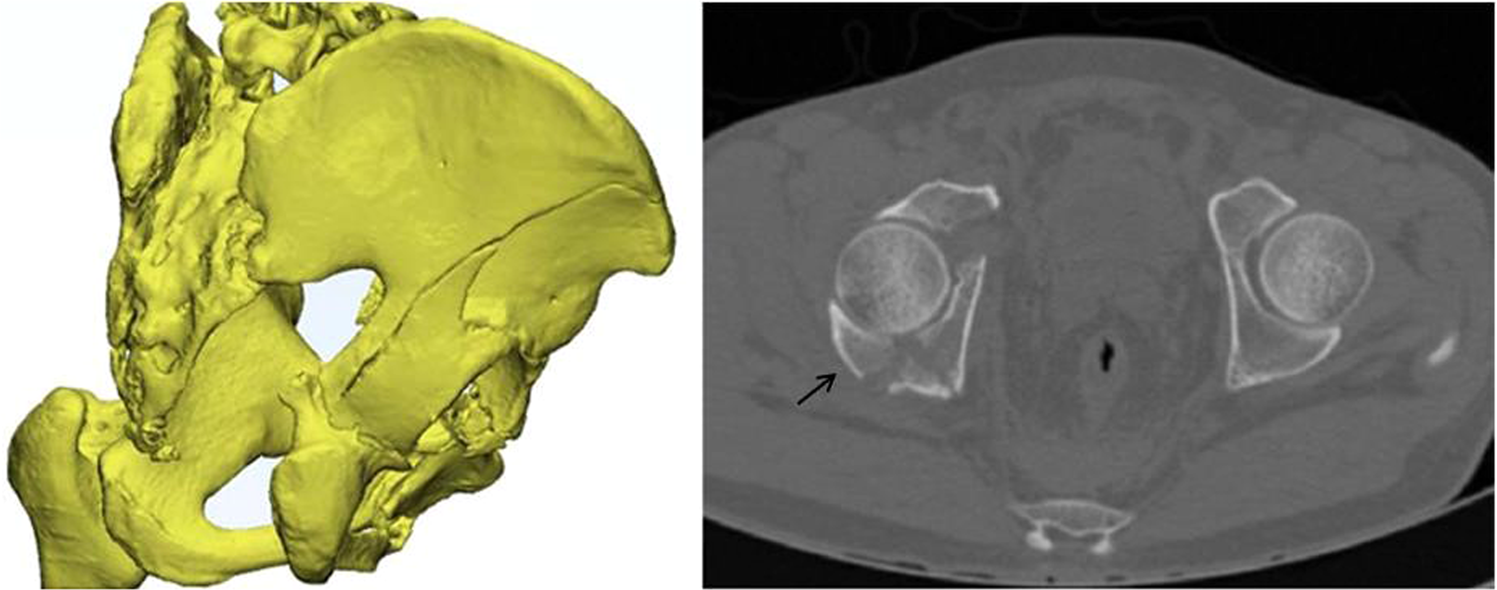

CT reconstruction and axial section images showing the posterior wall fragment associated with a both-column acetabular fracture.